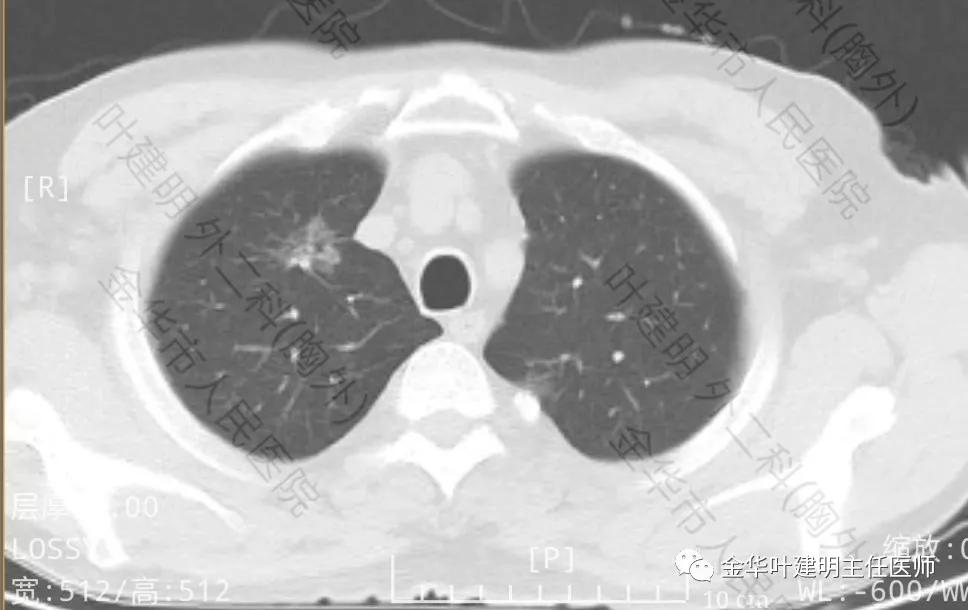

金华的阚某,今年67岁,前些日子因为“咳嗽、咳痰”到金华市人民医院就诊,因为考虑肺部感染,建议其住院抗炎治疗及进一步完善胸部CT等检查,结果示:右肺上叶磨玻璃结节,建议靶扫描及病理学检查;两肺多发感染性病变;左下支气管扩张等诸多肺部疾患。其CT检查影像如下:

上图示右上叶磨玻璃结节